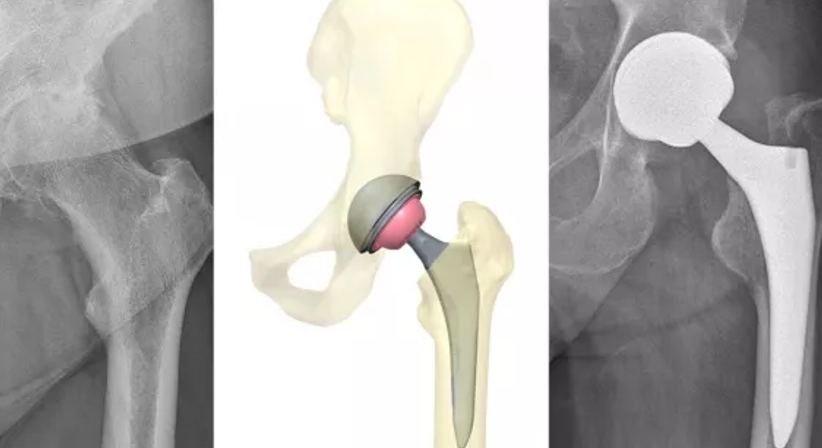

Die Implantation einer Hüftprothese (künstliches Hüftgelenk) erfolgt in den meisten Fällen bei einer konservativ austherapierten und schmerzhaften Coxarthrose (Hüftgelenksarthrose). Weitere Gründe einer H-TEP (= Hüft-Hüfttotalendoprothese) stellen die Hüftkopfnekrose oder die Folgen einer Verletzung der Hüfte dar.

Im Rahmen einer Hüftoperation werden alle Bestandteile des geschädigten Hüftgelenks durch künstliche Materialien ersetzt. Dabei kommen Implantate aus Titanlegierungen und Keramik zum Einsatz, welche dem internationalen Standard entsprechen.